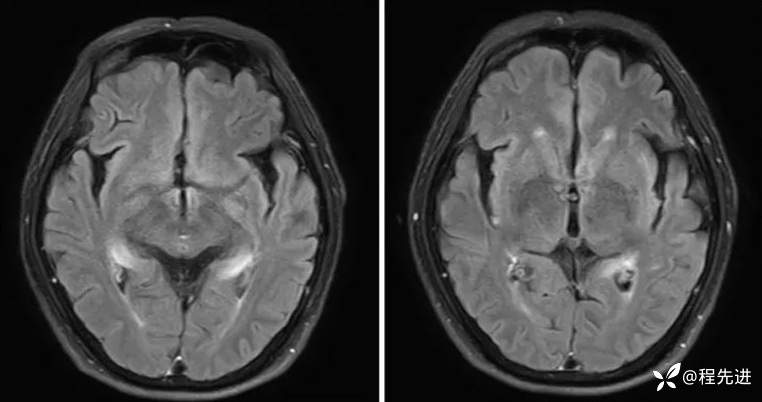

MRI平扫+增强:

FLAIR:

DWI、ADC: